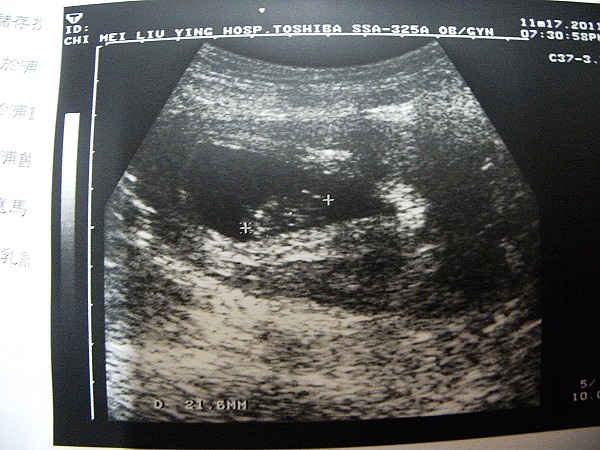

100.11.17「10w+1」

正式產檢了

醫生確定只有一顆心跳無誤

我最蝦操心的事情也總算放下心

去做了第一次的抽血檢測